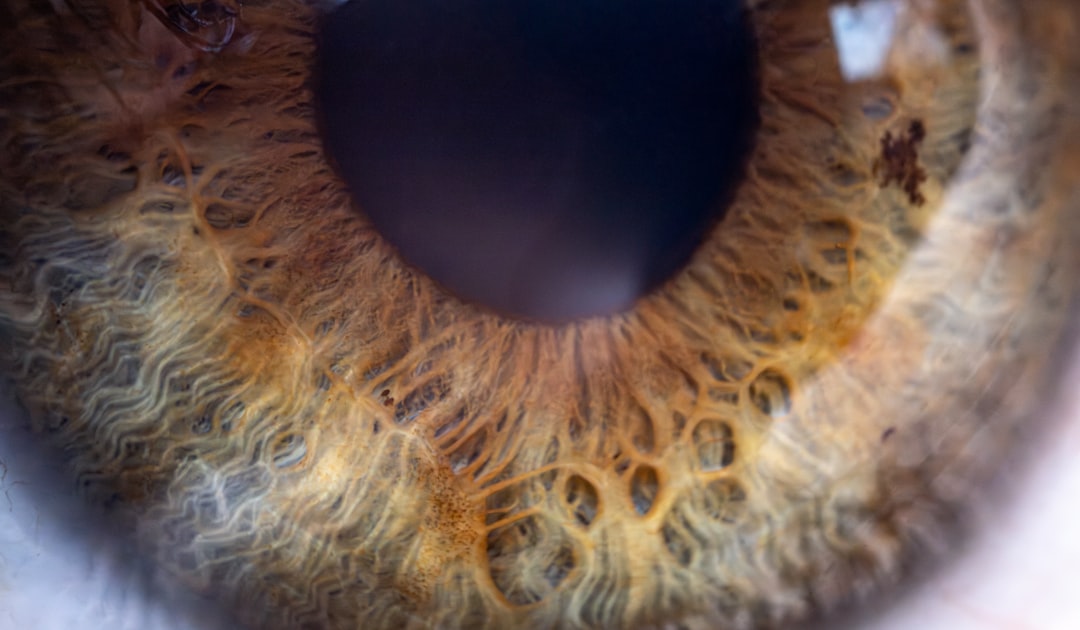

백내장은 눈의 수정체가 뿌옇게 변하는 질병으로, 시력 저하의 주요 원인 중 하나입니다. 이는 나이가 들면서 자연스럽게 발생할 수 있지만, 당뇨병, 외상, 유전적 요인 등 여러 원인으로 발생할 수 있습니다. 사람이 백내장에 걸리면, 흐릿해진 시야 때문에 일상적인 활동이 어려워질 수 있습니다. 이로 인해 많은 분들이 정기적인 검진과 치료를 통해 적시에 조치를 취하는 것이 중요합니다. 그렇게 접근하면 백내장을 더 이상 두려워하지 않아도 됩니다.